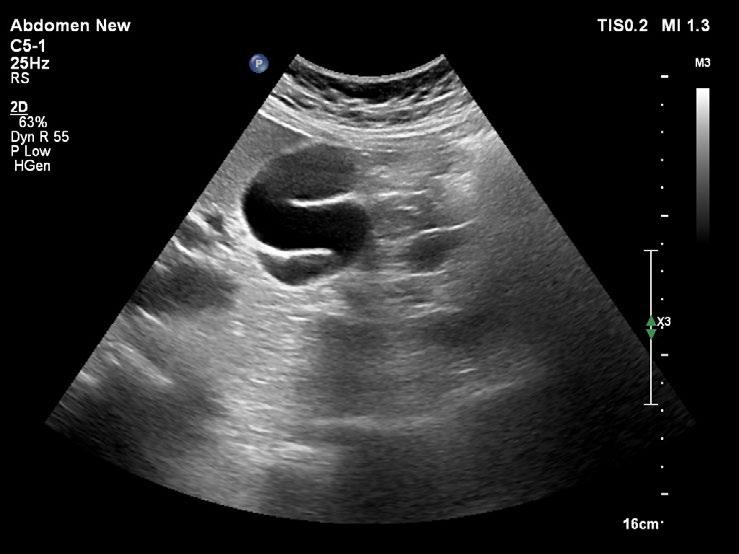

Kromě běžného kapkovitého tvaru mívá žlučník řadu tvarových variací. Časté je zahnutí žlučníku v oblasti krčku (obr. 1.4), těla (obr. 1.5) nebo fundu. Zahnutí bývá mnohdy i několikanásobné (obr. 1.6) a může v některých rovinách zobrazení vytvářet falešný dojem septace (obr. 1.7). Skutečné septum žlučníku je ale vzácné (0,02 % pitevních nálezů). Nalézá se například při duplikatuře žlučníku, při které je lumen rozděleno podélným septem a každá z polovin žlučníku je drénována vlastním ductus cysticus. Ohyb v infundibulu a krčku může imitovat dilataci hepatocholedochu (obr. 1.8). Při nízce odstupujícím ductus cysticus se ohyb krčku žlučníku může sumovat s hlavou pankreatu a vytvářet mylný dojem dilatace intrapankreatické části hepatocholedochu. Pečlivé vyšetření hlavy pankreatu a celého průběhu hepatocholedochu ve vícero zobrazovacích rovinách vede k odlišení ohybu žlučníku od vlastního nedilatovaného intrapankreatického hepatocholedochu (obr. 1.9).

Překlopení fundu žlučníku vytváří obraz frygické čapky (obr. 1.10, obr. 1.11). Žlučník tvaru frygické čapky je relativně častý (až 6 %). Raritním nálezem je dvojlaločný žlučník nebo divertikl žlučníku.